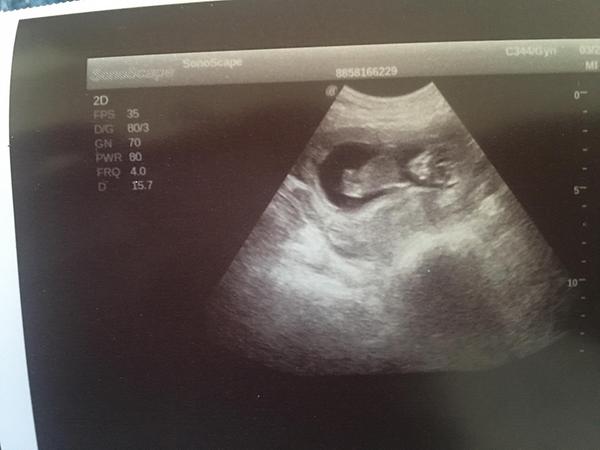

Je to holčička nebo chlapeček? Foto ultrazvuku

@lilian2111 já se v těch hrbolcích vůbec,ale vůbec nevyznám hah 😀 😀 ale pamatuji si u kluků,že ten pinďour šel vidět jasněji na těch prvních screeningách než teď u malého Damiánka či Dominička 😀 😀

@juliemichal škoda, že ta fotka je rozmazana. Ale vypadá to spíš na kluka, opravdu tam něco trčí, ale na tento týden by to byl tedy už poradny chlapak 😃 až půjdete v tom 15+4, poproste o fotku pohlaví ze spodu, to už by mělo být pohlaví poznat.

@kajda3 no to je fakt na 12+1 by to byl pořádný chlapák hah,takže to co tam trčí to určitě nebude šula 😀 😀 ale uvidíme ♥ ♥ určitě v úterý poprosím dr aby mi dala fotečku pohlaví ♥ ♥

@sebinka123 kéž by ta první fotka (screening) podle dr to vypadá na kluka,druhá fotka 2 dny později u mého gynekologa ten mi řekl,že mezi nožičky nic nevidí,že by ho zajímalo kde doktor viděl chlapečka 😀 😀 ale,že z největší pravděpodobností mi pohlaví řekne až ve 20tt

@juliemichal to jsem na tebe zvedava! 😁 musíš nám dat v úterý hnedka vědět. První fotka bych řekla na 99% kluk, ale ta druha zase vypadá na holčičku. Moc bych ti tu holčičku prala 🙂

jinak koukej první foto 14+5 tj dnes,druhé foto 14+1 třetí těhotenství s Mateem 😀 😀 a mám ty břicha úplně jiné u kluků jsem měla úplně stejné jako u Matea a teď fakt úplně jiné 😀 😀

@eiram7 jasná holčička, gratuluji 💃ve 13. týdnu je to jisté tak na 95 % 😊 navíc k tomu tento snímek hrbolek ukazuje pěkně 👍